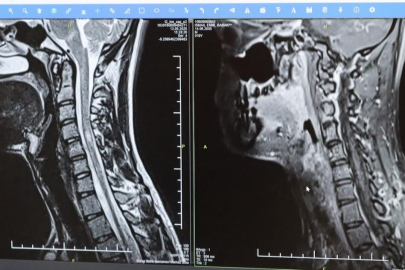

https://www.bbursa.com

MS hastalarının çeşitli şikâyetlerle hekimlere başvurduğunu vurgulayan Kamışlı, "Bunlar arasında görme bozukluğu, kol ve bacakta kuvvetsizlik, uyuşmalar, dengesizlik, yürüme bozukluğu, idrar problemleri veya aşırı yorgunluk ve halsizlik hali bulunmaktadır. MS ataklarla seyredebilir ve genellikle en sık görülen formu budur. Birdenbire bir şikâyet ortaya çıkar ve zamanla azalır veya kaybolur. Bir de progresif dediğimiz ilerleyici formu vardır. Bu ilerleyici formda hastalık yavaş yavaş ilerlemektedir. MS her hastada farklı seyreder. Bu nedenle tek tip bir MS hastalığından bahsetmek mümkün değil" şeklinde konuştu.